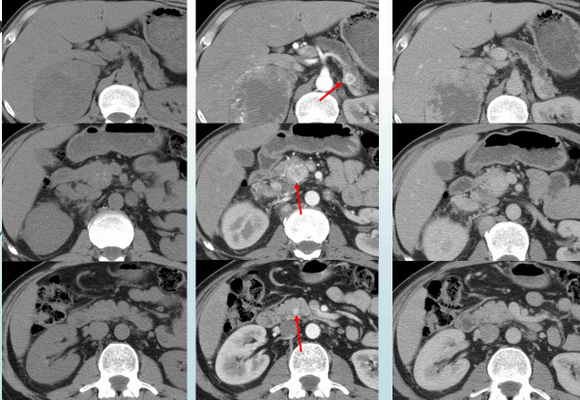

Рисунок 1. Множественные нейроэндокринные опухоли поджелудочной железы. Определяются только на фоне внутривенного введения контрастного препарата.

(Слева) На КТ в артериальной фазе контрастного усиления в шейке поджелудочной железы определяется объемное образование, активно накапливающее контраст (нейроэндокринная опухоль). Вышележащие отделы поджелудочной железы в значительной степени атрофированы что не является типичным признаком нейроэндокринных опухолей, которые чаще всего не становятся причиной обструкции панкреатического протока и атрофии паренхимы поджелудочной железы.

(Справа) На аксиальной КТ в венозной фазе контрастного усиления у этого же пациента опухоль по-прежнему накапливает контраст, но в значительно меньшей степени, чем в артериальной фазе. (Слева) На аксиальной КТ с контрастным усилением определяется кистозное образование в хвосте поджелудочной железы. В этом случае нельзя исключать внутрипротоковую папиллярно-муцинозную опухоль или муцинозную кистозную опухоль, но периферический характер контрастного усиления и наличие мягкотканного компонента, накапливающего контраст, позволяет сделать заключение о кистозной нейроэндокринной опухоли.

(Справа) На корональной КТ с контрастным усилением визуализируется гиповаскулярное объемное образование в крючковидном отростке поджелудочной железы на фоне многочисленных метастазов в печени.Опухоль прорастает в верхнюю брыжеечную вену, что не типично для аденокарциномы, и больше характерно для нейроэндокринной опухоли. (Слева) На аксиальной КТ в артериальной фазе контрастного усиления визуализируется массивная гиперваскулярная нейроэндокринная опухоль, практически полностью замещающая поджелудочную железу. Несиндромные опухоли, как в этом случае, часто имеют большие размеры на момент их обнаружения.

2. КТ признаки нейроэндокринной опухоли поджелудочной железы:

• Объемное образование ПЖ неинфильтративного характера с четкими контурами, которое обычно (но не всегда) является гиперваскулярным и наиболее хорошо заметно в артериальной фазе:

о В венозной фазе чаще всего накапливают контраст не так интенсивно, из-за чего небольшие опухоли сложно различить:

- Могут становиться заметнее в венозной фазе (редко)

о Синдромальные опухоли обычно имеет меньшие размеры на момент обнаружения (о Несиндромные опухоли больше на момент их обнаружения (их средний размер >5 см):

- Обычно являются гиперваскулярными, но не в такой степени, как синдромальные опухоли

- В крупных опухолях вероятнее наличие центрального некроза, кистозных изменений, кальцинатов

• В нейроэндокринных опухолях часто обнаруживаются кальцинаты (в центре или с диффузным распределением)

• В большинстве случаев НЭО (за исключением крупных) не приводят к панкреатобилиарной обструкции и атрофии паренхимы вышележащих отделов поджелудочной железы:

о Редко некоторые небольшие опухоли могут продуцировать серотонин, что приводит к фиброзу и обструкции протока поджелудочной железы (ППЖ)

• Опухоль чаще прорастает в воротную или верхнюю брыжеечную вену, а не охватывает их

• Кистозные нейроэндокринные опухоли могут имитировать другие кистозные новообразования поджелудочной железы:

о Периферическое нодулярное накопление контраста в артериальной фазе является характерным признаком нейроэндокринной опухоли

• Многофазная КТ с контрастным усилением или МРТ: наиболее важными являются изображения, полученные в артериальной фазе контрастного усиления